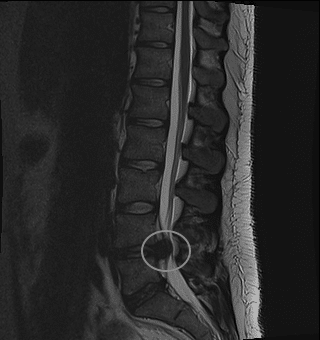

Magnetic resonance imaging (MRI) is arguably the most sophisticated imaging method used in clinical medicine. In recent years, MRI scans have become increasingly common, as costs decrease. In this article, we will outline the basic principles behind MRI scans, how to orientate and interpret a scan, and address some of their advantages and disadvantages compared to other imaging modalities. Pro Feature - 3D Model You've Discovered a Pro Feature Access our 3D Model Library Explore, cut, dissect, annotate and manipulate our 3D models to visualise anatomy in a dynamic, interactive way. Learn More Basic Principles MRI scans work as an imaging method due to the unique make-up of the human body. We are comprised entirely of cells which all contain water – principally made of hydrogen ions (H2O). The magnet embedded within the MRI scanner can act on these positively charged hydrogen ions (H+ ions) and cause them to ‘spin’ in an identical manner. By varying the strength and direction of this magnetic field, we can change the direction of ‘spin’ of the protons, enabling us to build layers of detail. When the magnet is switched off, the protons will gradually return to their original state in a process known as precession. Fundamentally, the different tissue types within the body return at different rates and it is this that allows us to visualise and differentiate between the different tissues of the body. <a href="https://pulseradeducation.com"> Pulse Radiology Education</a> Fig 1MRI scanning is based on the excitation and relaxation of protons. Uses of MRI Scanning Magnetic resonance imaging can produce highly sophisticated and highly detailed images of the human body. Generally speaking, MRI scanning is excellent for visualising soft tissue – and so it is often used in the detection of tumours, strokes and bleeds. It also can be used to visualise the functionality of suspected masses and tumours through IV, gadolinium-based agents. MRI scans have many advantages. As stated previously, they provide excellent detail of the soft tissues of the body, and they do not cause any radiation exposure to the patient. However, they are time consuming – averaging approximately 35-45 minutes to complete. This limits their use in trauma and emergency situations, where CT scanning is often preferred. They are also by far the most expensive of all the imaging modalities available. Factor CT (CT abdo used as example) MRI X-ray (CXR used as example) Ultrasound Duration 3-7 minutes 30-45 min 2-3 min 5-10 minutes Cost Cheaper Expensive Cheap Cheap Dimensions 3 3 2 2 Soft tissue Poor detail Excellent detail Poor detail Poor detail Bone Excellent detail Poor detail Excellent detail Poor detail Radiation 10mSv None 0.15mSv None At present, there are no known long lasting adverse effects from MRI scans. However, MRI safety has recently become a major focus in hospital and outpatient environments due to the potential attraction to ferromagnetic objects and devices. Some medical and implantable devices are considered contraindications for MRI evaluation – such as cardiac pacemakers, heart monitors, defibrillators and other battery-operated devices. Interpreting a MRI Scan Image View MRI scans, much like computed tomography, typically produce three anatomical views; sagittal, coronal and axial (similar to the planes of the body). When interpreting axial views, it is important to appreciate that the image is viewed from the feet upwards – and so the left-hand side of the image refers to the patient’s right (and vice versa). <a href="https://pulseradeducation.com"> Pulse Radiology Education</a> Fig 2The three main views obtained when MRI scanning. Left to right: Sagittal, coronal and axial. Image Weight Once the view of the scan has been determined, the second step is to work out the weight of the image. The magnetic fields produced by the scanner can be manipulated to produce two distinct types of image – T1 weighted and T2 weighted. The resulting images will show different tissue types in different densities: Appearance T1 Weighted Image T2 Weighted Image White Fat Protein Rich Fluid Water Content E.g. Inflammation, Tumour, Haemorrhage, Infection Intermediate Gray Spinal Matter darker than White White Spinal matter darker than gray spinal matter. Dark Bone Air Water Content e.g. Inflamation, Tumour, Haemorrhage Bone Air Fat Note: It can help to remember that a T tWo weighted image shows Water as White. Clinical Relevance Spinal Cord Compression Magnetic resonance imaging can be used to assess the extent of cord compression, when there is a suspicion of stenosis, disc herniation or cauda equina. The figure below shows a T2 weighted, sagittal MRI of the lumbar spine. The thecal sac is easily visible as the 1cm thick white band running posterior to the vertebral bodies. This is interupted at the L4/L5 level by a small round dark area, which is the herniation of the intervertebral disc into the central canal. By TeachMeSeries Ltd (2025) Fig 3Sagittal plane T2 weighted MRI Scan of lumbar spine, demonstrating disc herniation at L4/5 level. Do you think you’re ready? Take the quiz below Pro Feature - Quiz Magnetic Resonance Imaging (MRI) Scanning Question 1 of 2 Submitting... Skip Next Rate question: You scored 0% Skipped: 0/2 1800 More Questions Available Upgrade to TeachMeAnatomy Pro Challenge yourself with over 1800 multiple-choice questions to reinforce learning Learn More Rate This Article